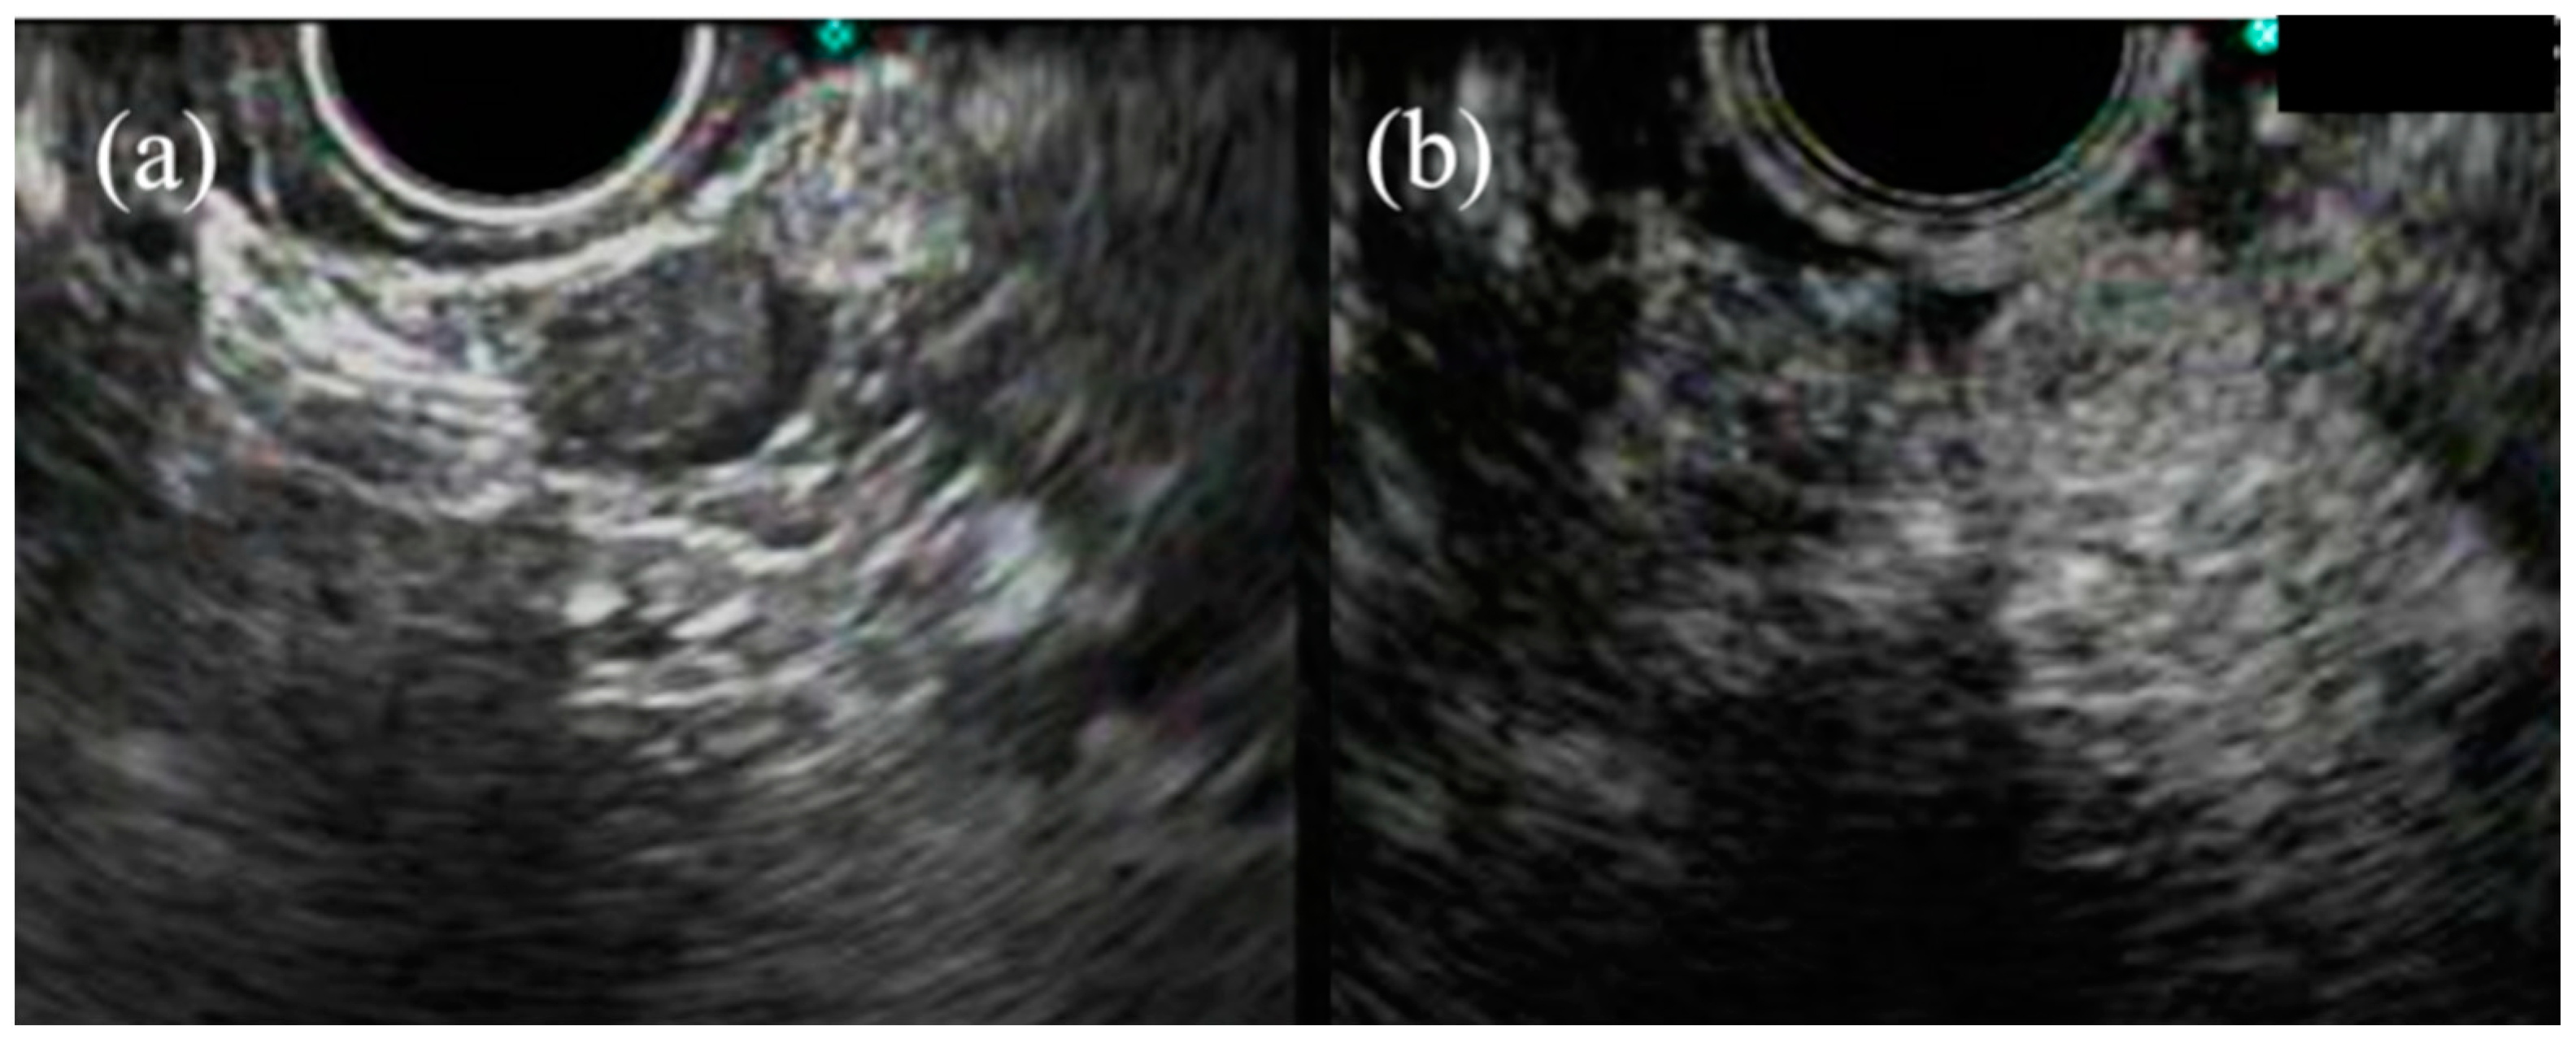

- Kim, G.H.; Kim, K.B.; Lee, S.H.; Jeon, H.K.; Park, D.Y.; Jeon, T.Y.; Kim, D.H.; Song, G.A. Digital image analysis of endoscopic ultrasonography is helpful in diagnosing gastric mesenchymal tumors. Bmc Gastroenterol. 2014, 14, 7. [Google Scholar] [CrossRef]

- Kim, G.H.; Park, D.Y.; Kim, S.; Kim, D.H.; Kim, D.H.; Choi, C.W.; Heo, J.; Song, G.A. Is it possible to differentiate gastric GISTs from gastric leiomyomas by EUS? World J. Gastroenterol. 2009, 15, 3376–3381. [Google Scholar] [CrossRef] [PubMed]